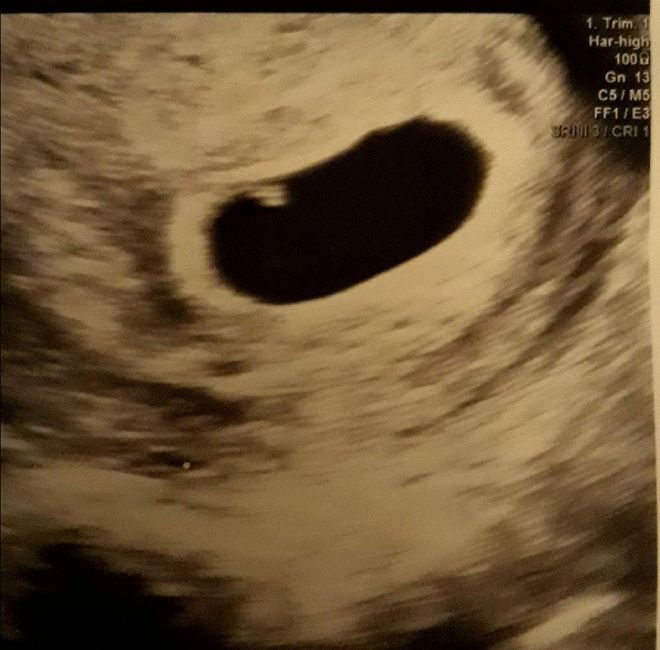

❤😊 ho rimandato perché la beta era a 870.000 e nel ecografia si vedeva un bel sacco vitellino non me la sono sentita di fare il raschiamento anche se per la mia ginecologa non mi a dato speranza ma il direttore prima di prepararmi per intervento mi a fatto un altra eco e si è vista meglio rispetto eco del altra stanza secondo lui sono indietro se volevo attendete visto che anche la beta e cresciuta ora attendo due settimane con la speranza ke cresca embrione con il battito secondo il mio calcolo oggi sono entrata a 6 settimane dal concepimento ma per il ginecologo lunedì ero a 9 settimane dal ultimo ciclo

Grazie Cristina nel eco si vedeva un puntino ma non era cresciuto dopo una settimana era sempre uguale lo spero con tutto il cuore ke lunedì si farà vedere cresciuto con la sacca del vitelino bel evidenziata nel precedente si intravedeva ma il ginecologo e convinto ke un uovo chiaro io sono convinta con la data della ovulazione ke ancora e presto lunedì dovrò essere a 5+5

Io purtroppo dovrò farlo lunedì per uovo chiaro ma non mi sento convinta visto ke ho concepito tra il 27 al 1 marzo secondo i loro calcoli dovrei stare 5.2 settimane no 8 settimane dal ciclo 😣lunedì mi fanno ultima eco spero ke stavolta spunta